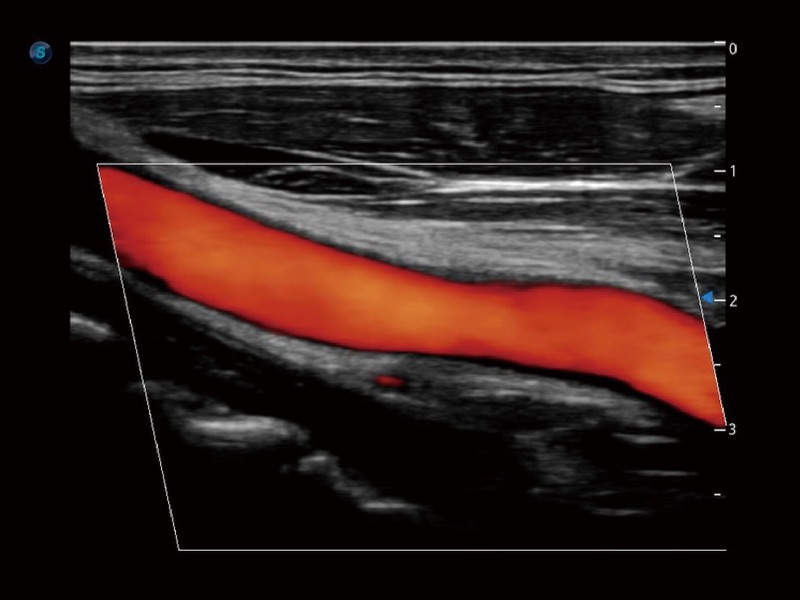

血管内中膜的厚度值是预测心血管疾病风险的重要指标,Auto IMT可以实现血管近场和远场内中膜厚度的自动测量,为临床提供快捷有效的诊断工具。

小器官应用